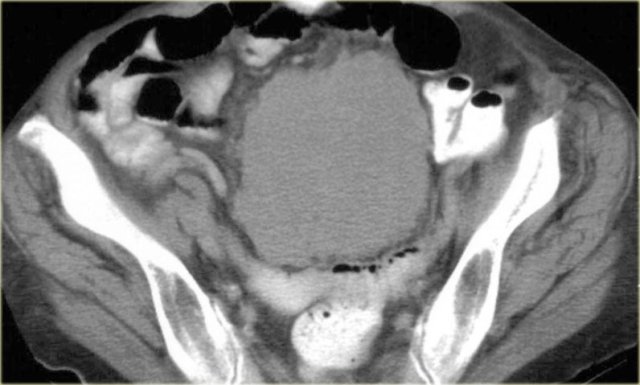

Peritoneal Inclusion Cyst

Also called Multilocular peritoneal inclusion cyst or Benign cystic mesothelioma.

This is an uncommon benign primary peritoneal tumor that has no relation with the malignant mesothelioma.

It occurs in premenopausal women with prior gynaecological surgery or infection that results in peritoneal scarring.

The hormonally active ovaries secrete fluid that becomes loculated in the pelvis.

The imaging features of a peritoneal inclusion cyst are non-specific except that it has to be located in the pelvis:

- Multicystic pelvic mass

- Enhancing septa

- Peritoneal surfaces of uterus, bladder

- May extend into upper abdomen

On the left a transvaginal ultrasound demonstrating a multicystic pelvic lesion next to the uterus, which proved to be a peritoneal inclusion cyst.

Sometimes the ovary is seen 'trapped' with the septate fluid collection (figure).